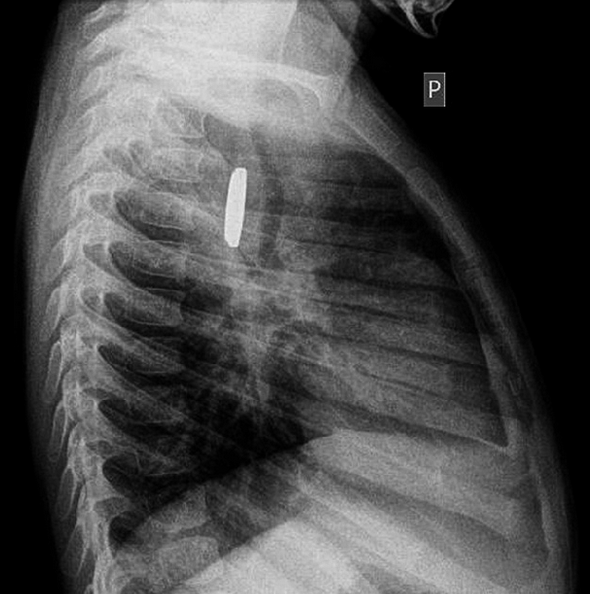

15 mon old without any complaints but the below, name the imaging test used to diagnosis this condition

What is Meckle's scan